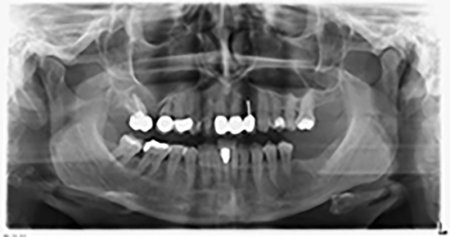

Al fine di pianificare e minimizzare i rischi, circa sei mesi dopo l'estrazione dei denti 16 e 14 viene effettuata una tomografia digitale volumetrica (DVT, Planmeca), la quale conferma chiaramente la mancata rigenerazione ossea nel volume desiderato (da fig. 2 a 7).